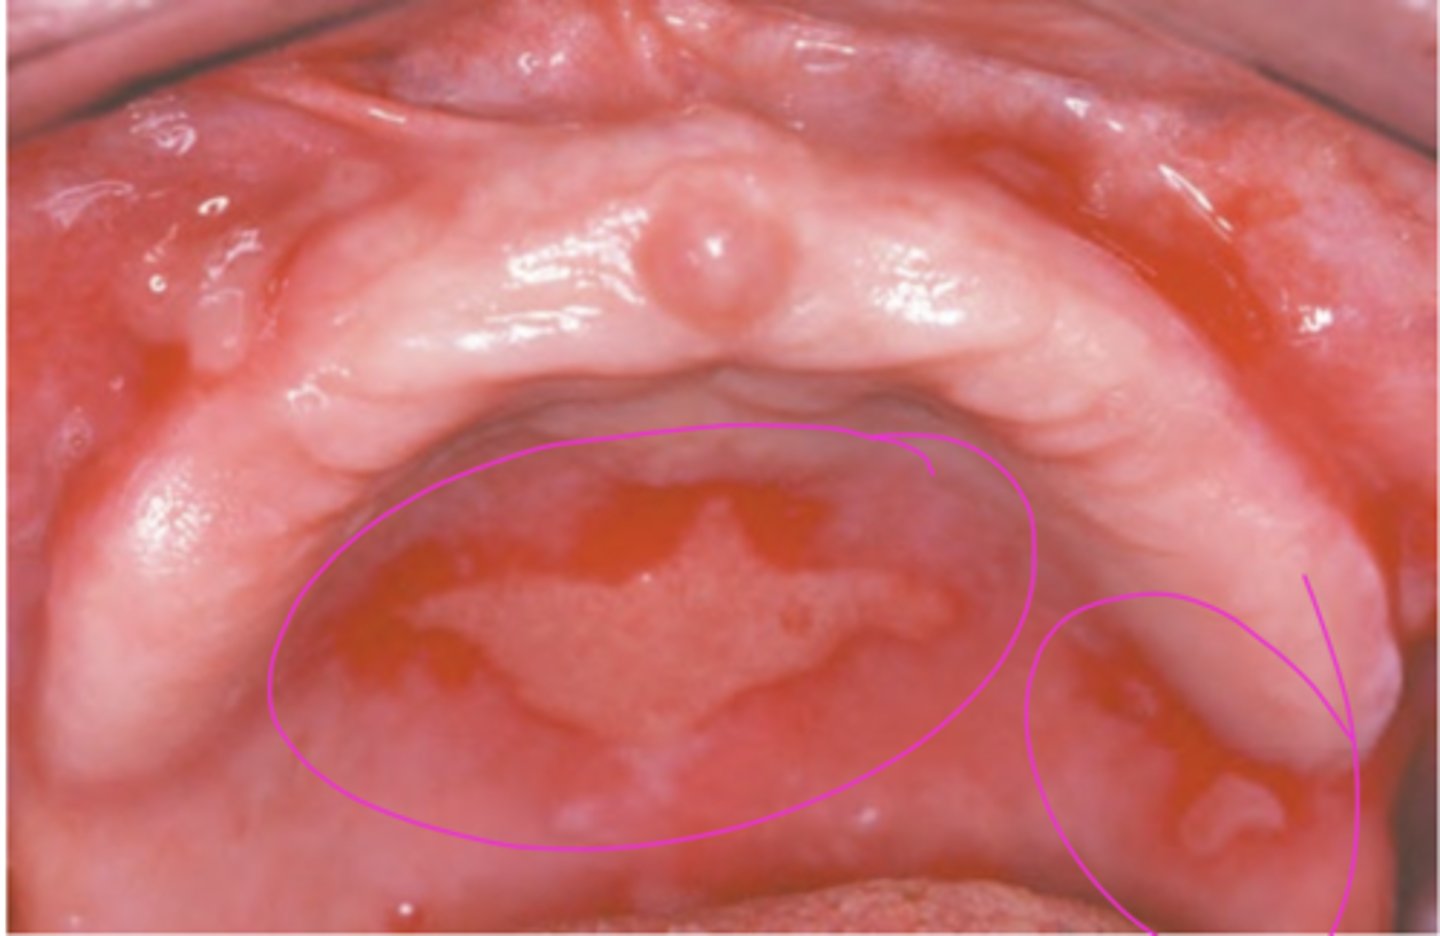

Squamous Cell Carcinoma (floor of mouth)

Diffuse erythematous speckled plaque on floor of mouth; most likely to arise from existing leukoplakia